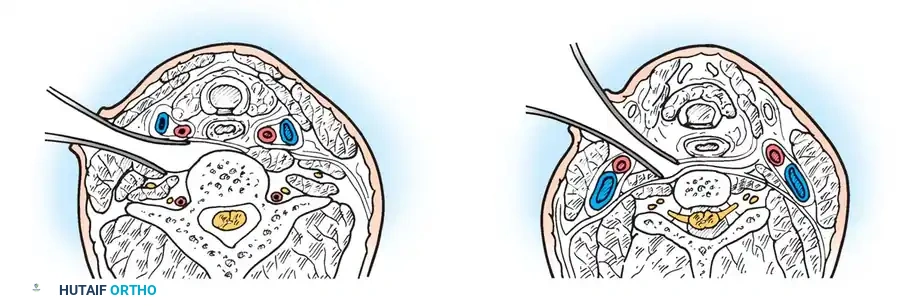

Dynamic Imaging and Instability Criteria:

Lateral flexion and extension radiographs are mandatory to document instability. In children, the free ossicle is fixed to the anterior arch of C1 and moves in unison with it. Therefore, measuring the relationship between C1 and the ossicle is futile.

Instead, instability is measured by projecting a line superiorly from the posterior body of the axis and measuring the distance to the posterior border of the anterior arch of the atlas.

* Significant Instability: > 3 mm in adults; > 4 to 5 mm in children.

* Space Available for the Cord (SAC): Measured from the posterior aspect of the odontoid/axis to the nearest posterior structure (posterior arch of C1). A SAC of < 13 mm is highly predictive of neurological injury.

Watanabe et al. defined specific radiographic parameters correlating with neurological symptoms:

1. Sagittal Plane Rotation Angle: > 20 degrees.

2. Instability Index: > 40%.

Image

Fig. 37-5 Radiographic parameters. Minimal (A) and maximal (B) distance from posterior border of body of C2 to posterior atlantal arch. C, Change of atlantoaxial angle between flexion and extension position. a, sagittal plane rotation.